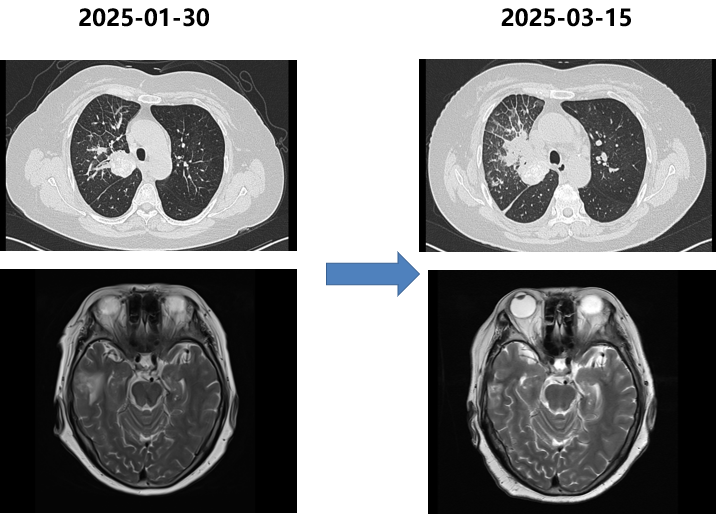

胸部CT和脑MRI(2025-01-30):肺部病灶进展,右侧脑转移病灶。

局部治疗放疗(2025-01-30开始):

右侧脑转移灶:SRT,PTV D95/30Gy/5F。

肺部病灶及纵隔淋巴引流区:IMRT(调强放疗),PGTV 60Gy,PTV 54Gy/30F。

胸部CT(2025-03-15):肺部病灶明显增大,实变范围扩大。

四次活检病理:小细胞神经内分泌癌。